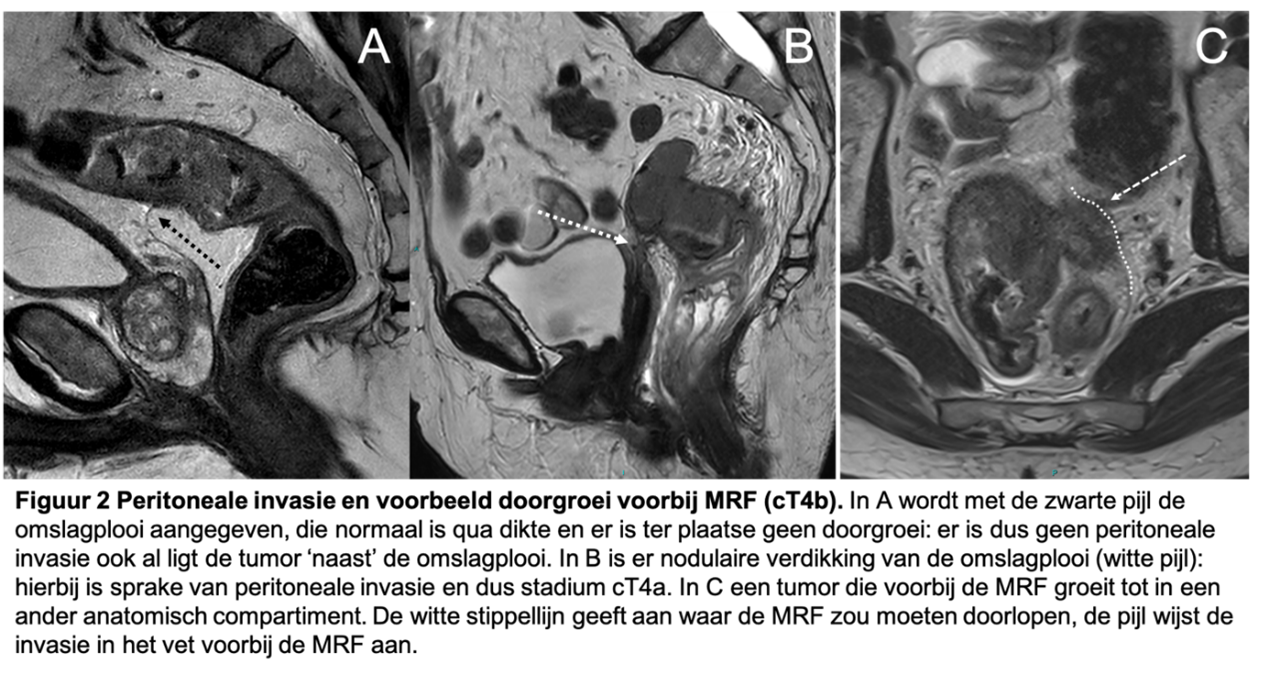

Relatie tot de mesorectale fascie en cT4

Bij peritoneale invasie ter plaatse van de omslagplooi is er sprake van een cT4a tumor. De omslagplooi is t.h.v. de rectosigmoid overgang tegen de darmwand aangelegen, aldus moet er (nodulaire of verdikte) zichtbare doorgroei in de omslagplooi zijn om een tumor als cT4a te kunnen classificeren. Een tumor zonder doorgroei in de omslagplooi is geen cT4a tumor (figuur 2).

Figuur 2. Peritoneale invasie en voorbeeld doorgroei voorbij MRF (cT4b)